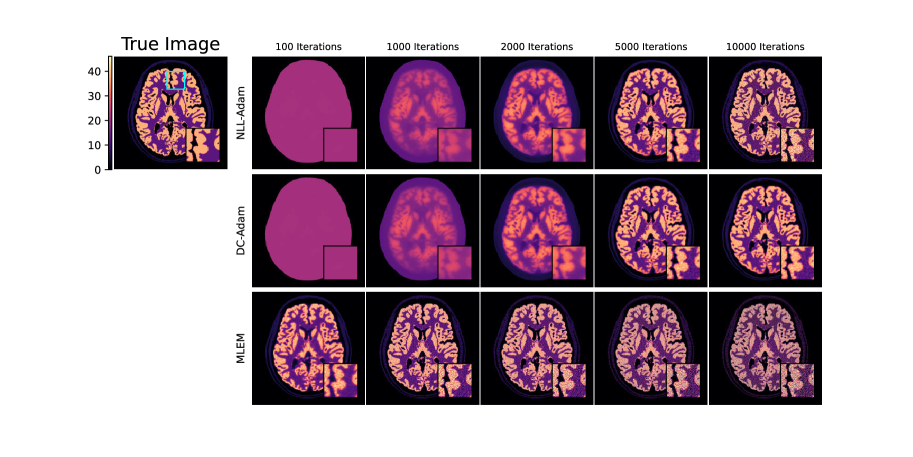

Refer to caption

Figure 6: PET image reconstructions formed with three iterative algorithms (NLL-Adam, DC-Adam and MLEM) shown with increasing iteration number. The proposed DC loss (row 2) clearly avoids the noise overfitting with NLL as an objective, whether with Adam optimization (row 1) or with the MLEM optimization algorithm (row 3).

In Figure 6, we show the visual results from each algorithm over 10,000 iterations. We see that both MLEM and NLL-Adam overfit to noise in the image, with varying convergence rates. We further see that DC-Adam does not overfit the noise in the data. This is also observed in Figure 7(a), where the NLL of the DC-Adam image plateaus after 2,000 iterations, and in Figure 7(b) where the NLL-Adam and MLEM images do not converge to zero DC loss. In Figure 7(c), we see that DC-Adam converges at the minimum error of NLL-Adam, although MLEM achieves a slightly better minimum error than both (likely due to the non-negativity constraint in the MLEM algorithm).

In this setting the problem is less over-parameterized than in Sections 5.1 and Appendix D, so perfectly fitting the noise is harder. Even so, DC loss delivers a clear advantage: it converges to its best solution and stays there, rather than briefly peaking and then chasing noise. In practice this yields stable late-iteration behavior without early stopping, fewer noise artifacts in highly iterated images, and better agreement with the assumed noise model. By contrast, conventional fidelity terms tend to overfit as iterations progress. Additional setup details and experiments on the impact of over-parameterization are provided in Appendix F.